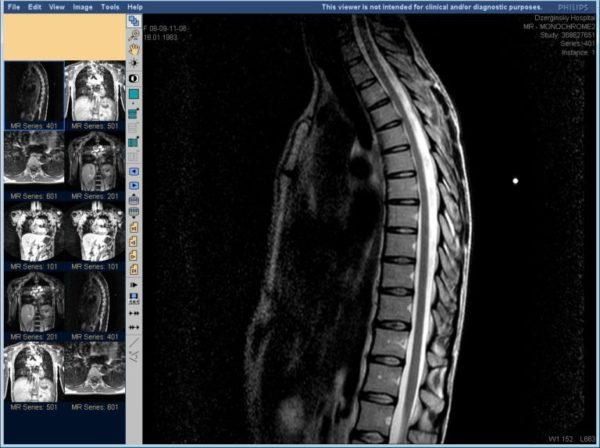

Что лучше: УЗИ позвоночника или МРТ

Пациенты, планирующие обследование позвоночника, часто сталкиваются с вопросом: выбрать МРТ или УЗИ. МРТ представляет собой компьютерное исследование, основанное на использовании магнитного резонанса атомов, составляющих человеческие ткани.

Часто УЗИ назначается в сочетании с другими методами диагностики, такими как МРТ. Хотя цель этих процедур одинакова, между ними существуют значительные различия. Но возможно ли провести только УЗИ позвоночника без использования МРТ

В отличие от УЗИ, при исследовании внутренних органов МРТ менее информативно, поэтому чаще используется для выявления патологий в костных тканях.

Тем не менее, стоит отметить, что ультразвуковой метод не способен обнаружить межпозвоночные грыжи в крестцовой области позвоночника. В то же время, магнитно-резонансная томография эффективно выявляет выпадение межпозвоночных дисков.

Однако для диагностики большинства других патологий позвоночного столба, о которых мы уже говорили, вполне достаточно использования только современного метода УЗИ. Поэтому не всегда имеет смысл переплачивать за проведение МРТ.